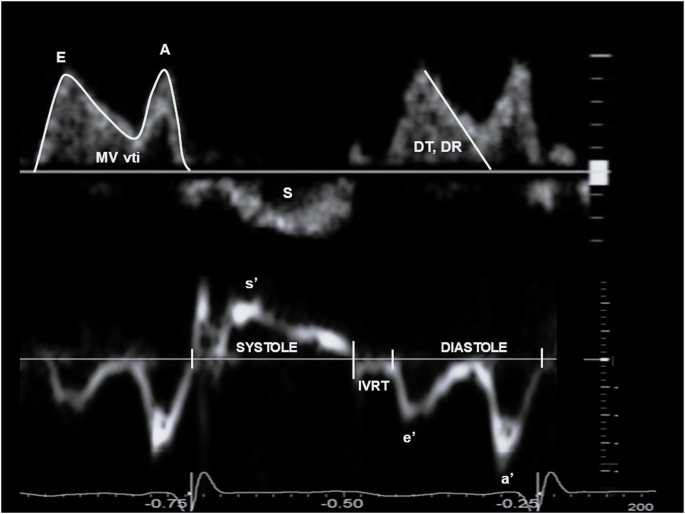

Images were acquired according to the recommendations of the American Society of Echocardiography and the targeted neonatal echocardiography recommendations and saved at 100 and 200 mm/s sweep speeds [8]. Ultrasound parameters of interest for multimodal LV diastolic function assessment are presented in Table 1, Figs. 1 and 2 and included cardiac size and shape, blood flow velocities, myocardial velocities and myocardial shortening. Most measurements were derived from a 3-beat average at 200 mm/s sweep speed. Partial fusion of the diastolic wave forms is common in preterm infants. When full fusion was apparent, we ensured the infant was settled using facilitated tucking and sucrose before further image acquisition was attempted. Doppler images with persistent full fusion between the early and late diastolic wave forms were omitted from analysis. Strain measurements were taken from apical 4-chamber images in adult orientation, from one heartbeat, and analysed by one investigator using a 6-segment (LV) or 3 segment (LA) model. Images were selected based on image quality criteria such as level of foreshortening, gain settings, clarity of borders, presence of artefacts, frame rate and tracking quality. Pulmonary vein Doppler was not part of our cardiac ultrasound protocol in this epoch.

S outflow wave, MV vti mitral valve velocity time integral, E early diastolic wave, A atrial contraction wave, DT deceleration time, DR deceleration rate, s’ systolic myocardial velocity, e’ early diastolic myocardial velocity, a’ atrial contraction myocardial velocity, IVRT isovolumetric relaxation time.